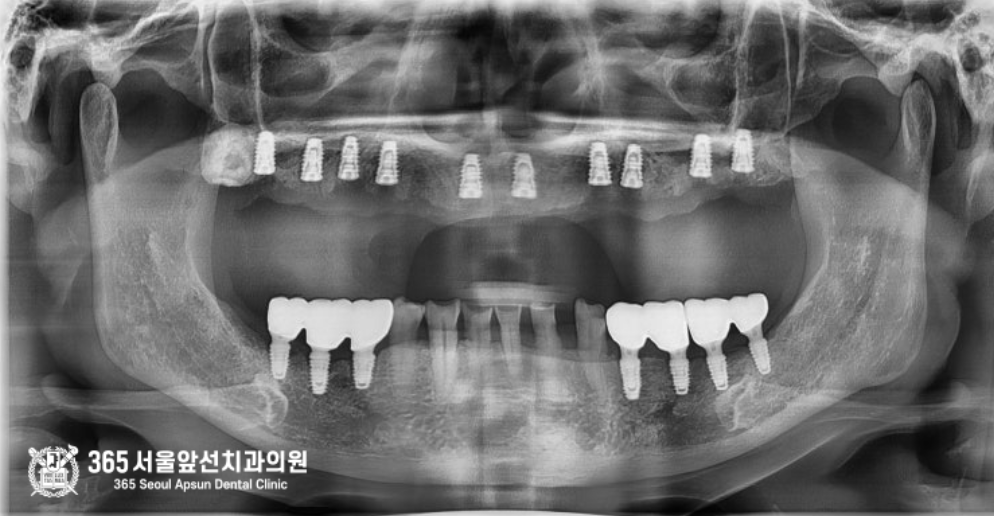

촬영일시 : 2025.05.10 처음 내원 당시 엑스레이 사진입니다. 사진상에 노란색 점선으로 표시한 곳이 뼈의 위치이며, 임플란트가 뼈 바깥으로 노출되어 심하게 흔들리고 오염된 상태였습니다. 이러한 경우 그대로 보철물을 만들 수도 없지만, 만든다고 한들 오래쓰지 못하기때문에 재수술을 하는 것이 옳은 치료법이 되겠습니다.